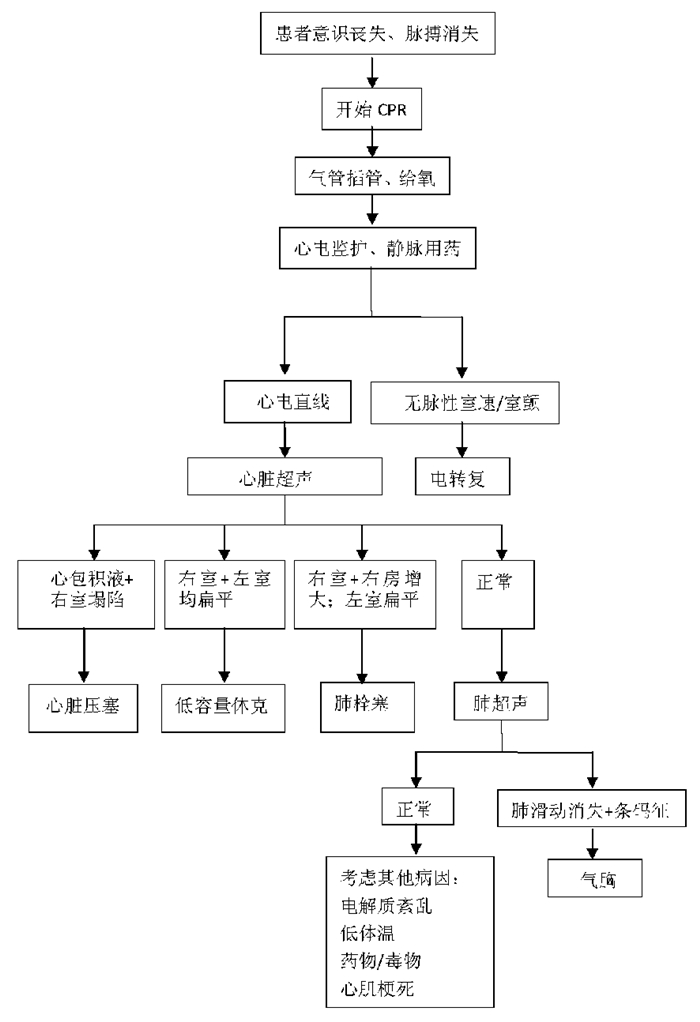

3.4.3 心肺复苏中超声诊断步骤及流程在心肺复苏中,为了避免超声检查对胸外按压的干扰,在心脏按压过程中实施心脏扫描,剑突下四腔心脏切面是最为理想的视窗。首先心脏超声可探及心脏运动(图 37),研究表明心脏骤停的患者被超声确认为心肌运动缺失的心搏停止时,其生存的希望极其渺茫。其次,超声检查还可以帮助寻找导致心脏骤停的可逆性病因。

具体超声诊断流程见图 38。

| 图 38 心脏骤停超声诊断流程 |